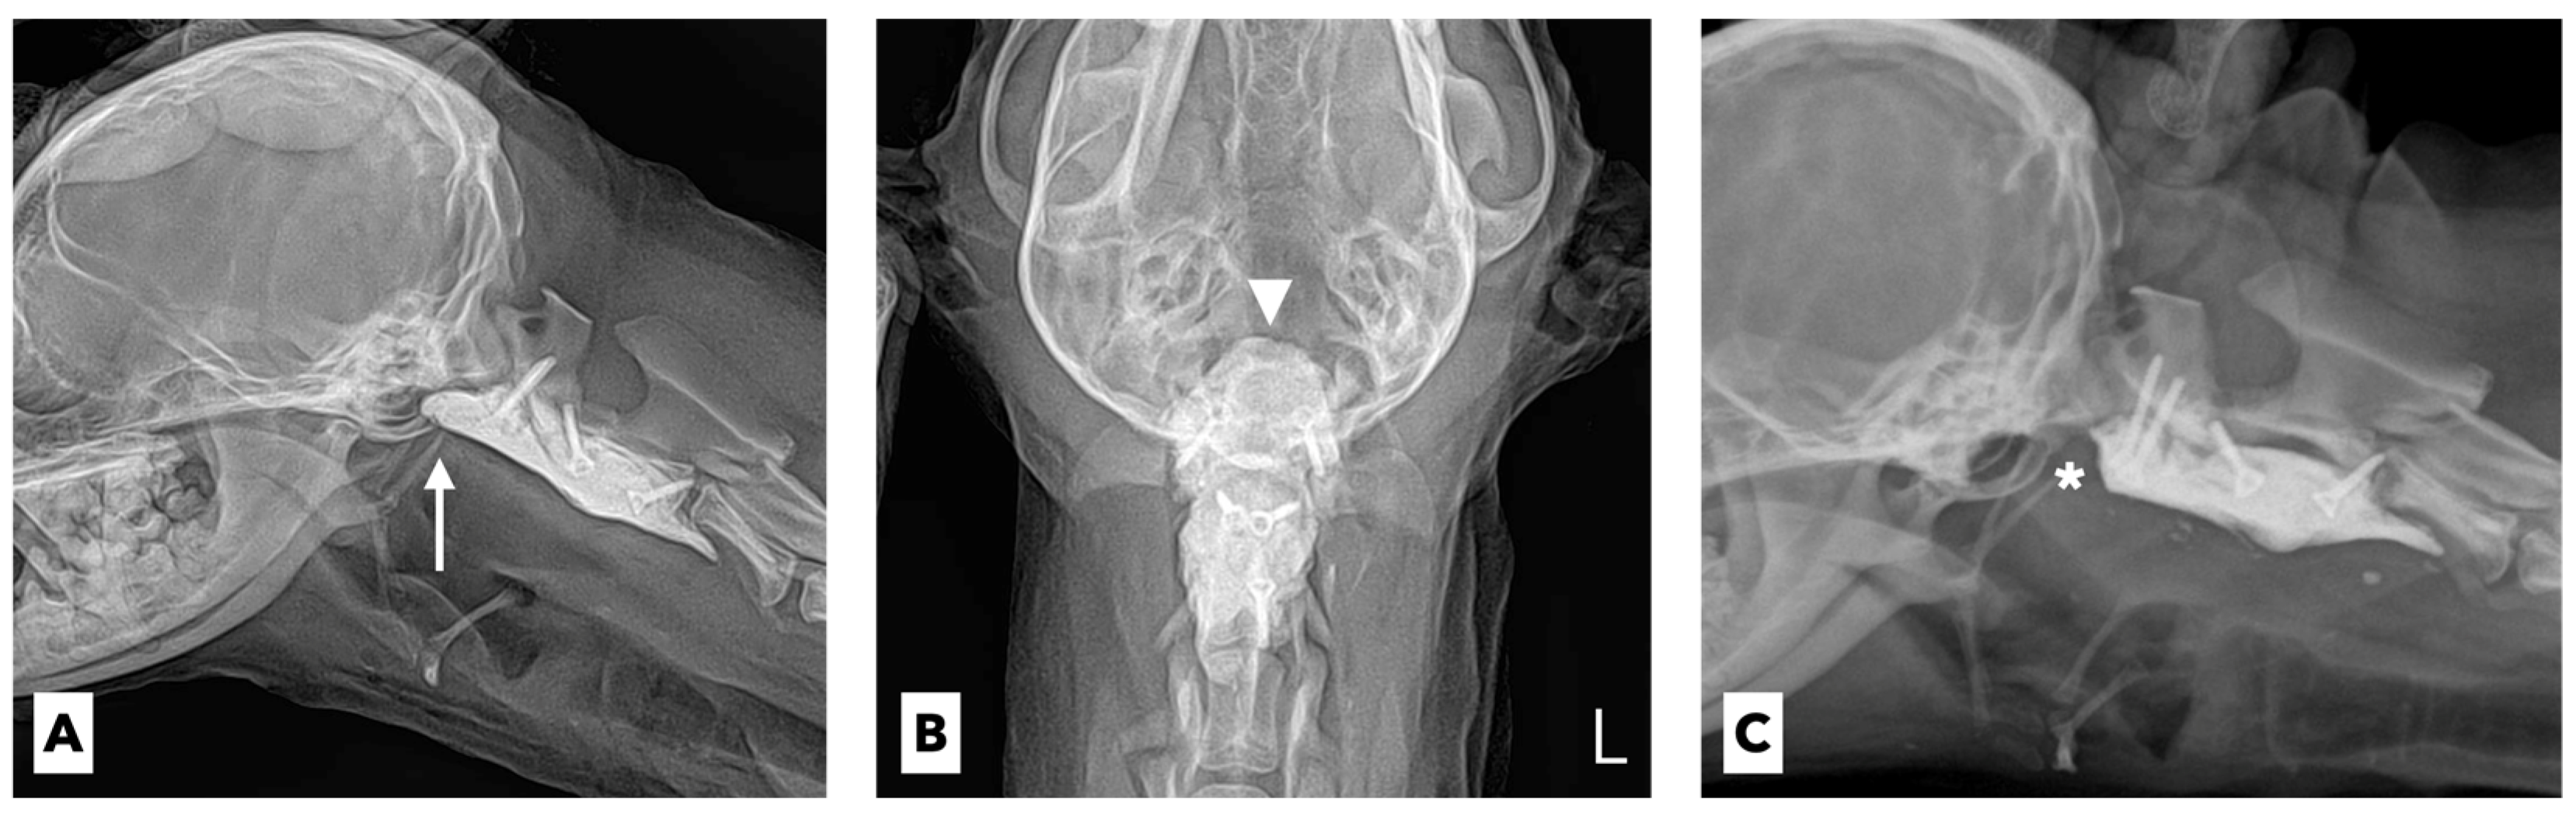

A 4-year-old spayed female miniature poodle dog weighing 3.1 kg presented with a 1-week history of acute tetraparesis. The dog was generally healthy until the clinical signs were observed. She had been fully vaccinated and dewormed, with no history of trauma or toxin exposure. The neurological examination revealed severe neck pain and tetraparesis with signs of upper motor neurons in the thoracic and pelvic limbs. Except for these neurological abnormalities, no other abnormalities were noted on the physical examination. The results of the complete blood-cell count (ProCyte Dx, IDEXX Laboratories, ME, USA) and serum biochemistry (Catalyst One Chemistry Analyzer, IDEXX Laboratories, ME, USA) were unremarkable. On the lateral flexed radiographs, the space between the spinous process of the axis and the dorsal arch of the atlas was increased (Figure 1A).

The dog underwent computed tomography (CT) and magnetic resonance imaging (MRI) to evaluate for suspected cervical myelopathy. The CT (Action 16-slice scanner, Toshiba Medical Systems, Otawara, Japan) revealed hypoplastic dens of the axis with prominent compression of the spinal cord at the levels of the first and second cervical vertebrae (Figure 1B). The MRI (Vantage Atlas 1.5-T scanner, Toshiba Medical Systems, Otawara, Japan) at the same anatomical level as the CT scan revealed that the spinal cord was moderately compressed, which in turn caused inflammatory changes in the adjacent spinal-cord parenchyma (Figure 1C). Based on these findings, congenital AAS with hypoplasia of the dens was diagnosed.

Figure 1. Lateral flexed radiographic image (A) showing that the space (arrow) between the spinous process of axis and the dorsal arch of atlas is increased. Sagittal-plane CT imaging (B) reveals a hypoplastic dens (arrowhead) of the axis with prominent compression of the spinal cord. T2-weighted magnetic resonance image (C) reveals moderately compressed spinal cord and inflammatory changes of the adjacent spinal cord parenchyma (asterisk).